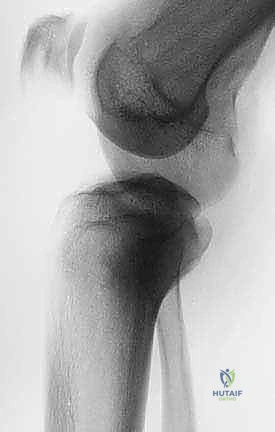

يُعد الشريان المأبضي (Popliteal Artery) بمثابة شريان الحياة الرئيسي للطرف السفلي. يمر هذا الشريان الضخم خلف مفصل الركبة مباشرة في منطقة تُعرف بالحفرة المأبضية (Popliteal Fossa). عند وصوله إلى الحافة السفلية للعضلة المأبضية، يتفرع هذا الشريان إلى شبكة معقدة تُعرف باسم "التشعب المأبضي ثلاثي الفروع" (Trifurcation)، وهي تتكون من:

يُعد الفهم العميق والدقيق لهذه التفرعات أمراً بالغ الأهمية ويفصل بين نجاح الجراحة أو فشلها الكارثي. أثناء عملية استئصال الورم من الظنبوب القريب، غالباً ما يضطر الجراح إلى التعامل بحذر شديد مع هذه الأوعية. في بعض الحالات، يتطلب الأمر ربط (Ligation) الشريان الظنبوبي الأمامي إذا كان الورم قريباً جداً منه، مع ضرورة تحديد وحماية الأوعية الأخرى (خاصة الشريان الظنبوبي الخلفي) لضمان استمرار إمداد الدم الكافي للساق والقدم بعد الجراحة، وتجنب خطر تموت الأنسجة (Ischemia). هنا تبرز أهمية مهارات الجراحة المجهرية التي يتقنها الأستاذ الدكتور محمد هطيف لضمان سلامة هذه الأوعية الدقيقة.

أثناء جراحة استئصال الظنبوب القريب، يتم حتماً استئصال الحدبة الظنبوبية مع الورم. هذا يعني أن آلية الباسطة تُفصل تماماً عن الساق. ولذلك، فإن التحدي الأكبر للجراح هو إعادة بناء هذه الآلية (Extensor Mechanism Reconstruction) وربط الرباط الرضفي بالطرف الصناعي المعدني بشكل قوي وفعال. يتم ذلك باستخدام شبكات صناعية خاصة (Synthetic Meshes) وتثبيتها بخيوط جراحية شديدة المتانة، بالإضافة إلى الاستعانة بالسديلة العضلية (Gastrocnemius Flap) لدعم هذا الاتصال. فشل هذه الخطوة يعني عدم قدرة المريض على رفع ساقه أو المشي بدون دعامة تقويمية مدى الحياة.